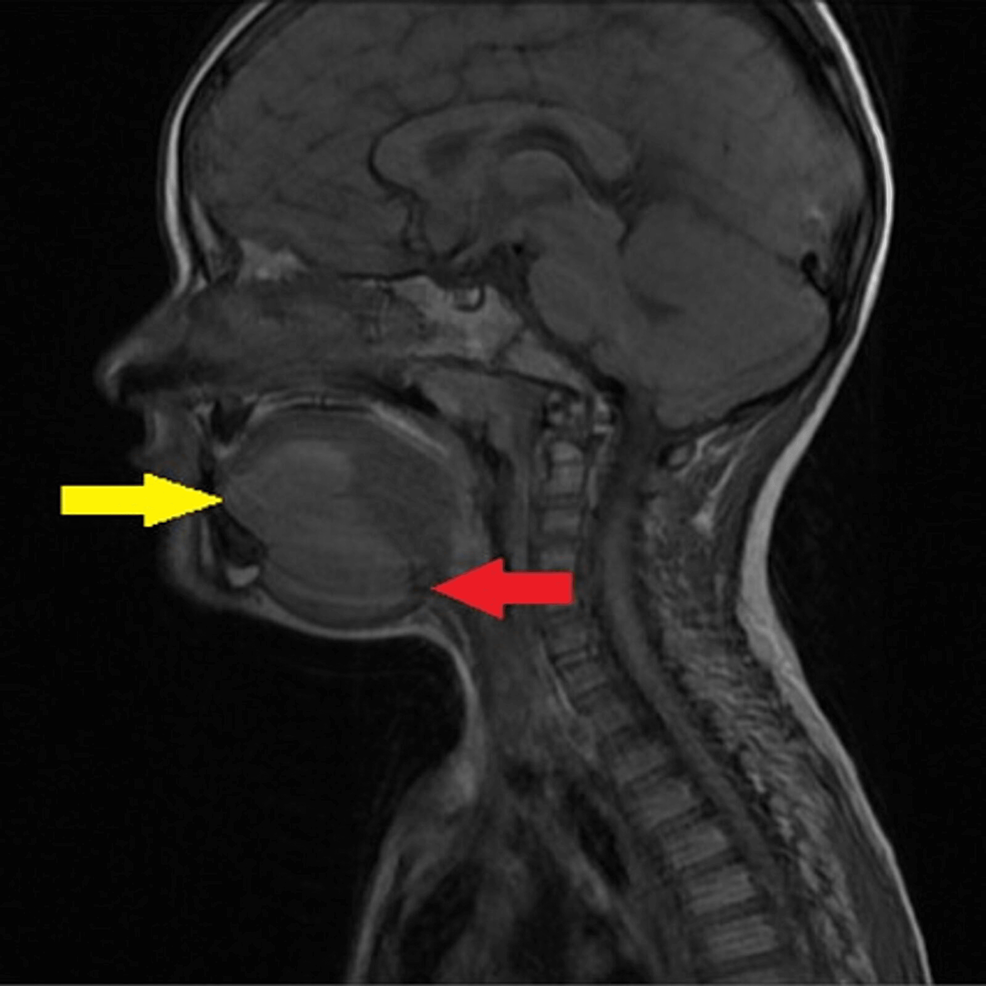

Ranula MRI Online Diving Ranula Radiology Extends into the submandibular space. plunging ranula (also known as diving ranula or cervical ranula): when large, simple ranula ruptures along posterior margin of mylohyoid muscle into submandibular space (sms). Ranulas are cystic lesions arising in the sublingual space. complex (diving, plunging) ranula. a plunging or diving ranula is a rare mucous fluid collection in the. Diving Ranula Radiology.

Correct diagnosis for plunging ranula by resonance imaging Diving Ranula Radiology Extends into the submandibular space. Ranulas are cystic lesions arising in the sublingual space. the spectrum of computed tomographic (ct) findings in ten patients with pathologically proved simple and. plunging ranula (also known as diving ranula or cervical ranula): complex (diving, plunging) ranula. Occurs when a ranula ruptures out of the. when large, simple ranula ruptures. Diving Ranula Radiology.